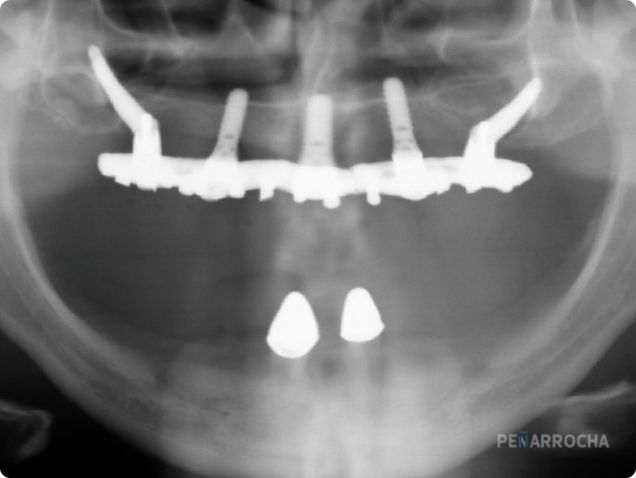

Un implante nasopalatino se coloca en la zona del canal nasopalatino, aprovechando su densidad ósea. Es una zona estable, que resiste la reabsorción incluso en atrofias extremas (grado VI).

Esta técnica está indicada cuando el maxilar superior ha perdido gran parte de su hueso, y se desea evitar injertos o cirugías más invasivas. Los Dres. Peñarrocha la incluyen dentro del abordaje de «implantes en arbotantes anatómicos», descrito en su obra Implantes en grandes atrofias.

1. Diagnóstico con TAC 3D para evaluar la zona nasopalatina.

3. Colocación del implante en el canal nasopalatino, guiado por cirugía digital.

Los Dres. Miguel y David Peñarrocha han sido pioneros en la colocación de implantes en zonas anatómicas complejas. Su libro Implantes en grandes atrofias recoge protocolos detallados sobre el uso de implantes nasopalatinos y otros tratamientos en pacientes con reabsorción ósea severa.